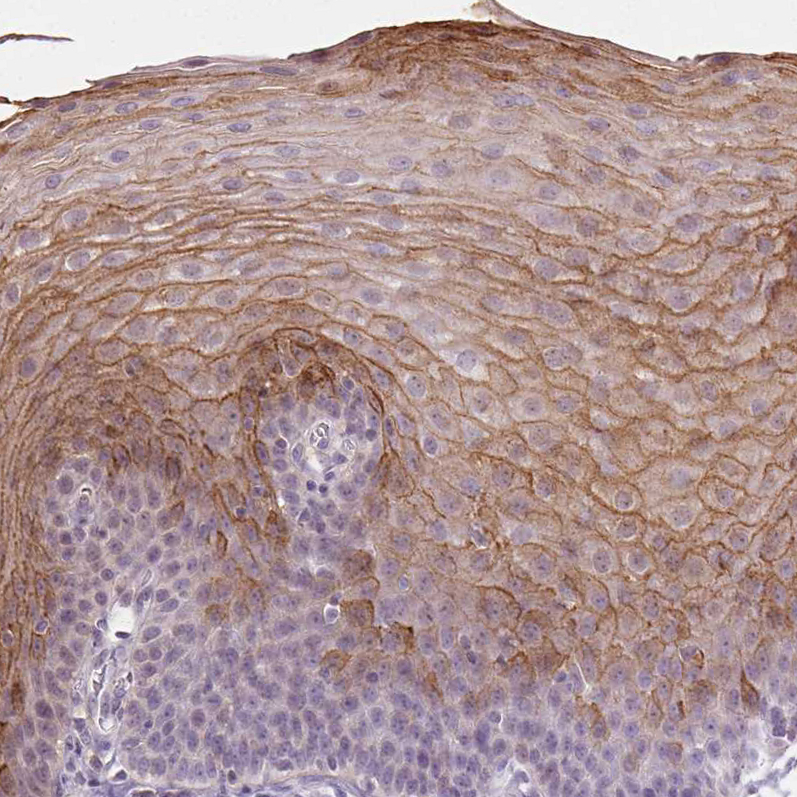

Immunohistochemistry analysis in human esophagus and liver tissues using HPA017737 antibody. Corresponding PI3 RNA-seq data are presented for the same tissues.